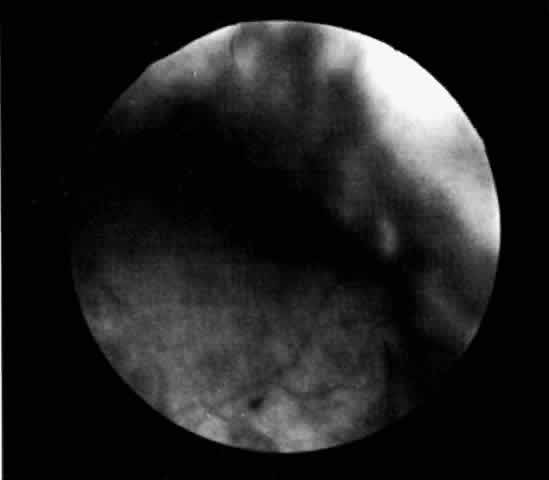

A ciliochoroidal effusion and other benign processes may be accurately differentiated from choroidal tumors with B-scan ultrasonography, as reported by Coleman29 in more than 60% of cases. Ultrasonography can distinguish a ciliochoroidal effusion from a retinal detachment by the acute anterior angle of the acoustic shadow of an effusion and its extension anterior to the ora serrata (Fig. 6). The ultrasonic finding of a diffusely thickened choroid posteriorly should alert the ultrasonographer and ophthalmologist to the possibility of a ciliochoroidal detachment more anteriorly. If posterior choroidal thickening is not associated with a peripheral ciliochoroidal detachment, other clinical entities should be excluded, such as posterior scleritis, choroidal inflammation, and intraocular tumors.30 Scleral infolding may ophthalmoscopically simulate a ciliochoroidal effusion in a hypotonous eye, and B-scan ultrasonography may assist in the diagnosis.31

Fig. 6. B-scan ultrasound of a choroidal effusion. An acute anterior angle and extension anterior to the ora serrata help to distinguish this as a choroidal effusion, rather than a retinal detachment.